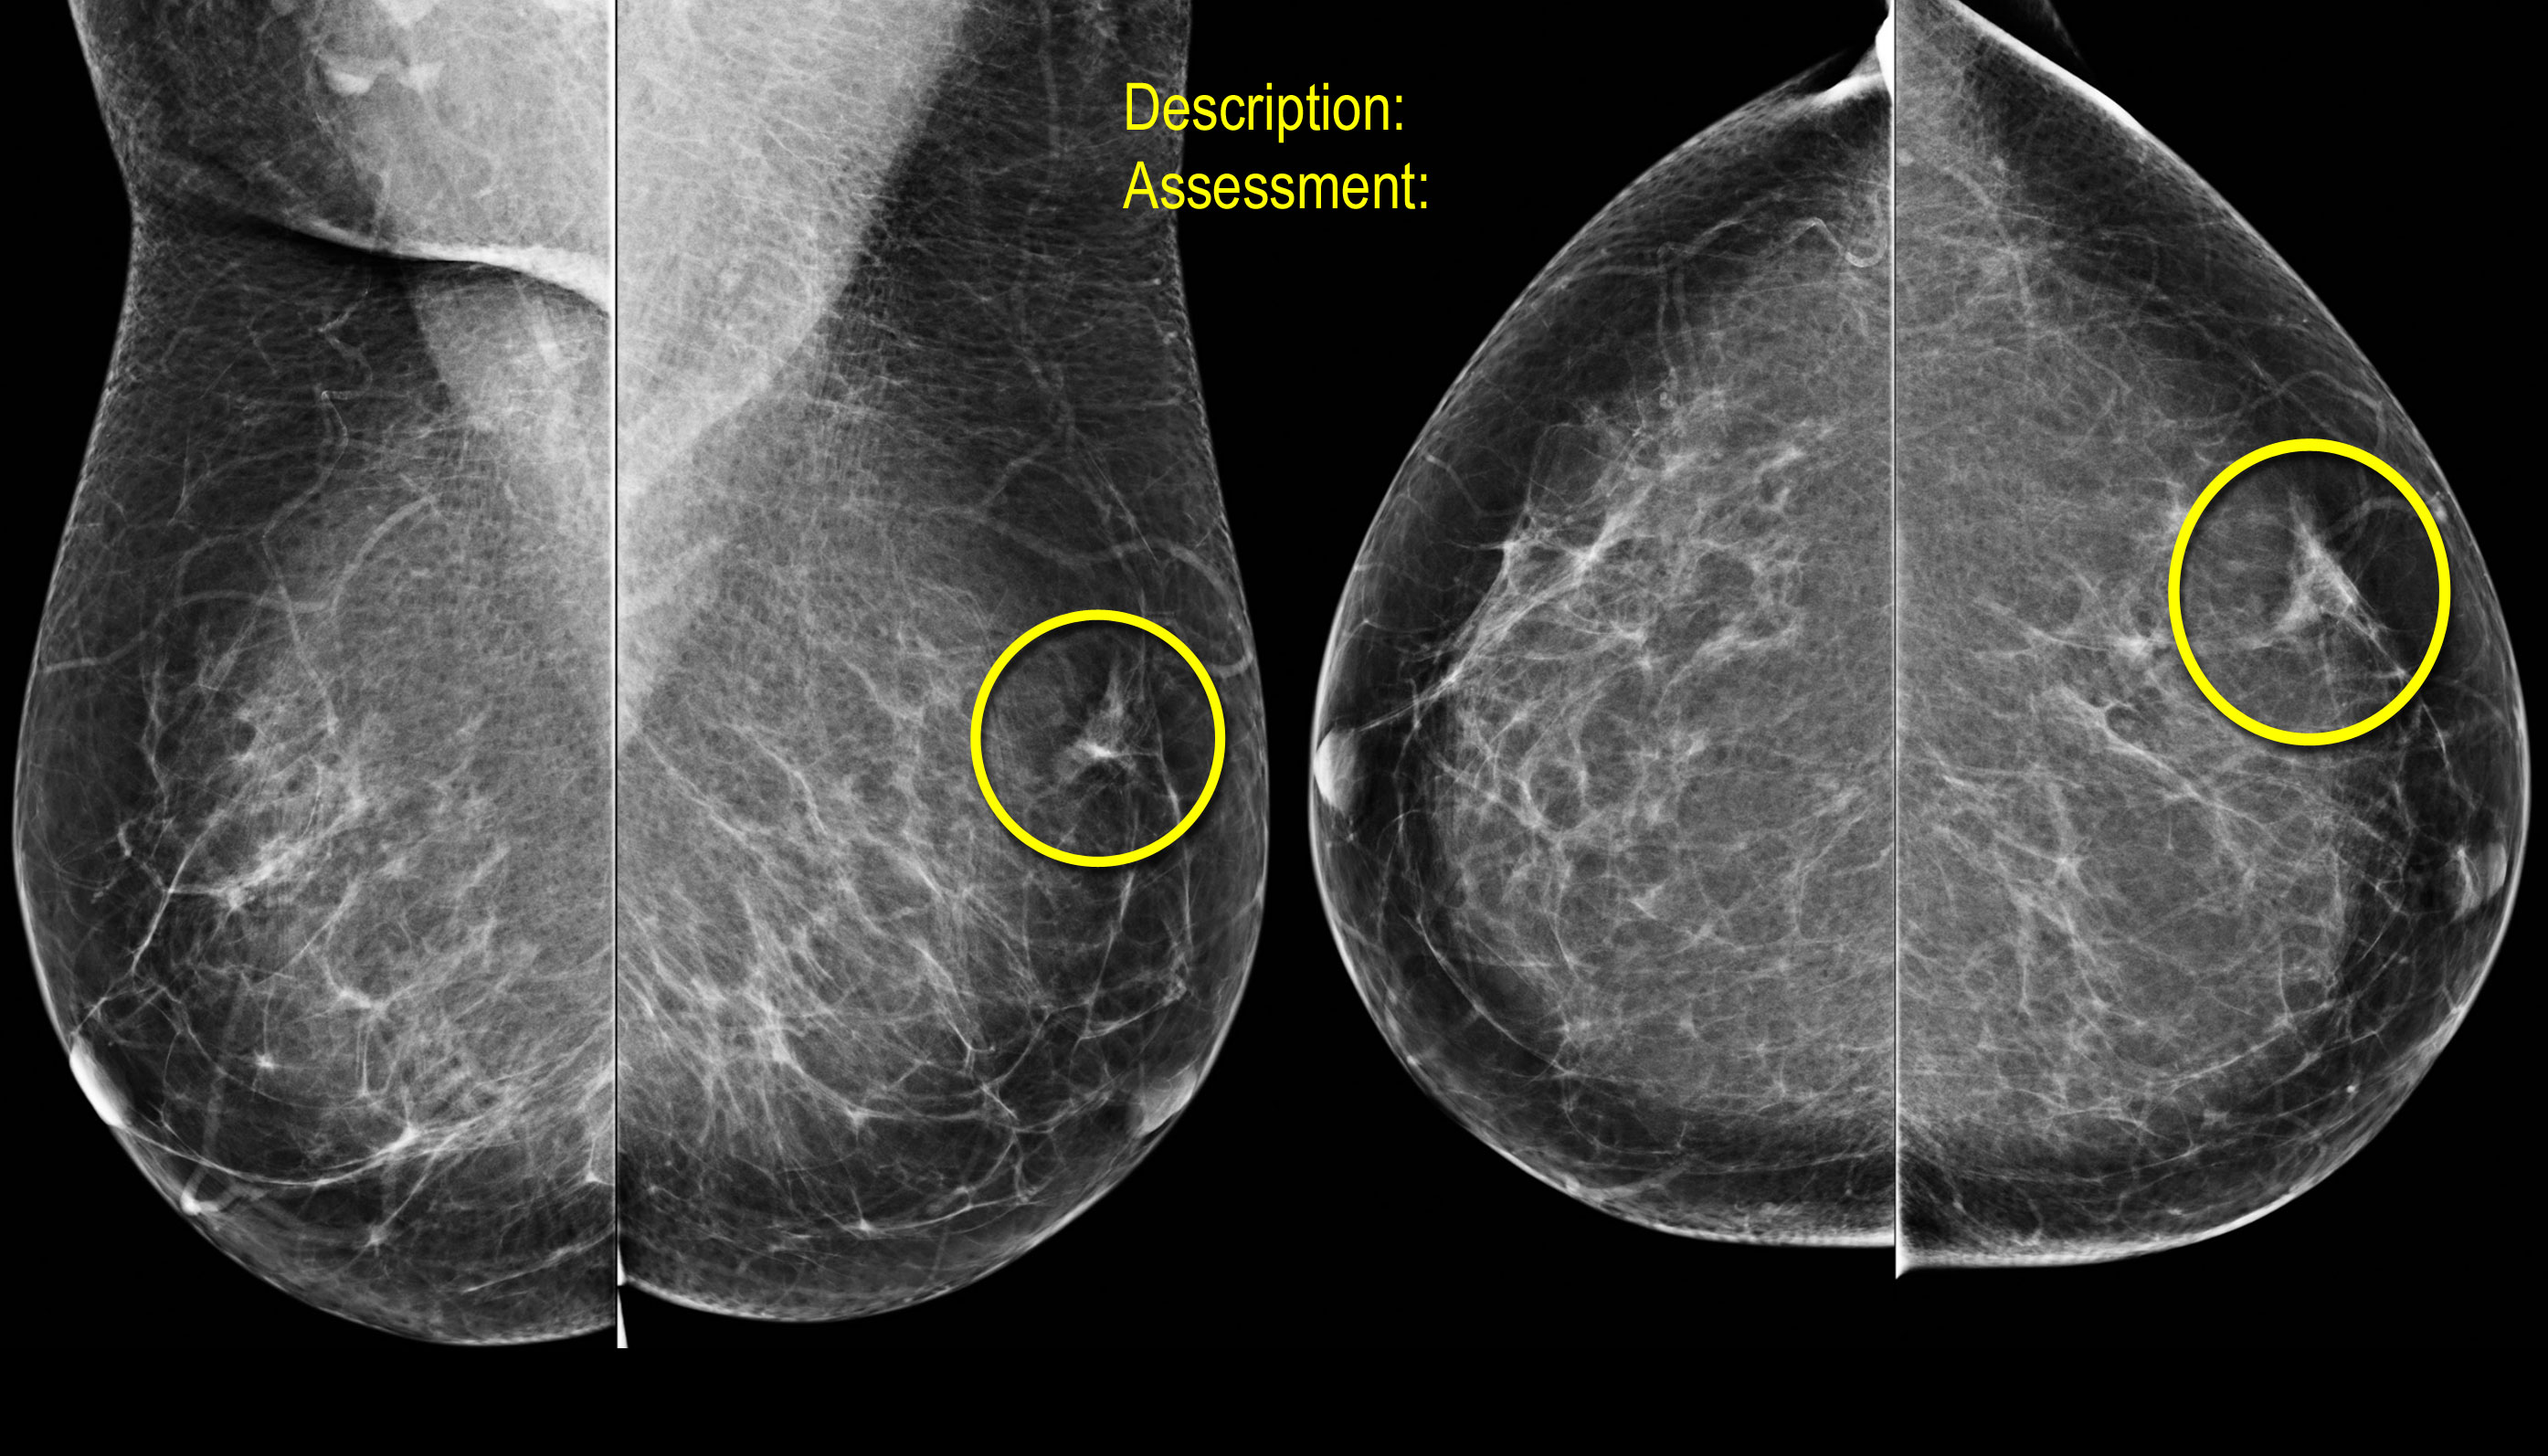

Quan sát và phân tích các hình ảnh.

Nếu phát hiện bất thường, hãy đưa ra mô tả và phân loại đánh giá tương ứng.

Biến dạng cấu trúc

Thuật ngữ biến dạng cấu trúc được sử dụng khi cấu trúc bình thường bị biến dạng mà không có khối rõ ràng nào được nhìn thấy.

Điều này bao gồm các đường thẳng mảnh hoặc các tua gai tỏa ra từ một điểm, và hiện tượng co rút khu trú, biến dạng hoặc thẳng hóa ở rìa nhu mô tuyến.

Chẩn đoán phân biệt bao gồm mô sẹo hoặc ung thư biểu mô.

Biến dạng cấu trúc cũng có thể được ghi nhận như một đặc điểm kèm theo.

Ví dụ, nếu có một khối gây biến dạng cấu trúc, khả năng ác tính sẽ cao hơn so với trường hợp khối không có biến dạng.

Lưu ý sự biến dạng cấu trúc vú bình thường trên tư thế chếch (vòng tròn vàng) và tư thế phóng đại.

Bệnh nhân đã được phẫu thuật cắt bỏ và chỉ tìm thấy mô sẹo trong bệnh phẩm.